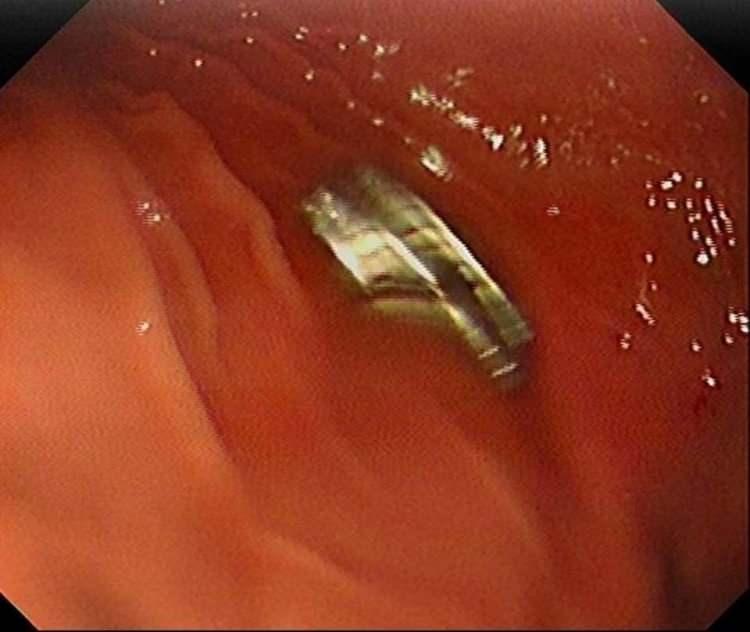

Midesinden 19 mıknatıs çıkarılan çocuk doktorları şoke etti!

Çocuğun rahatsızlanması sonucu durumu öğrenen aile hastaneye başvurdu. Daha sonra çocuk Elazığ’a sevk edildi.